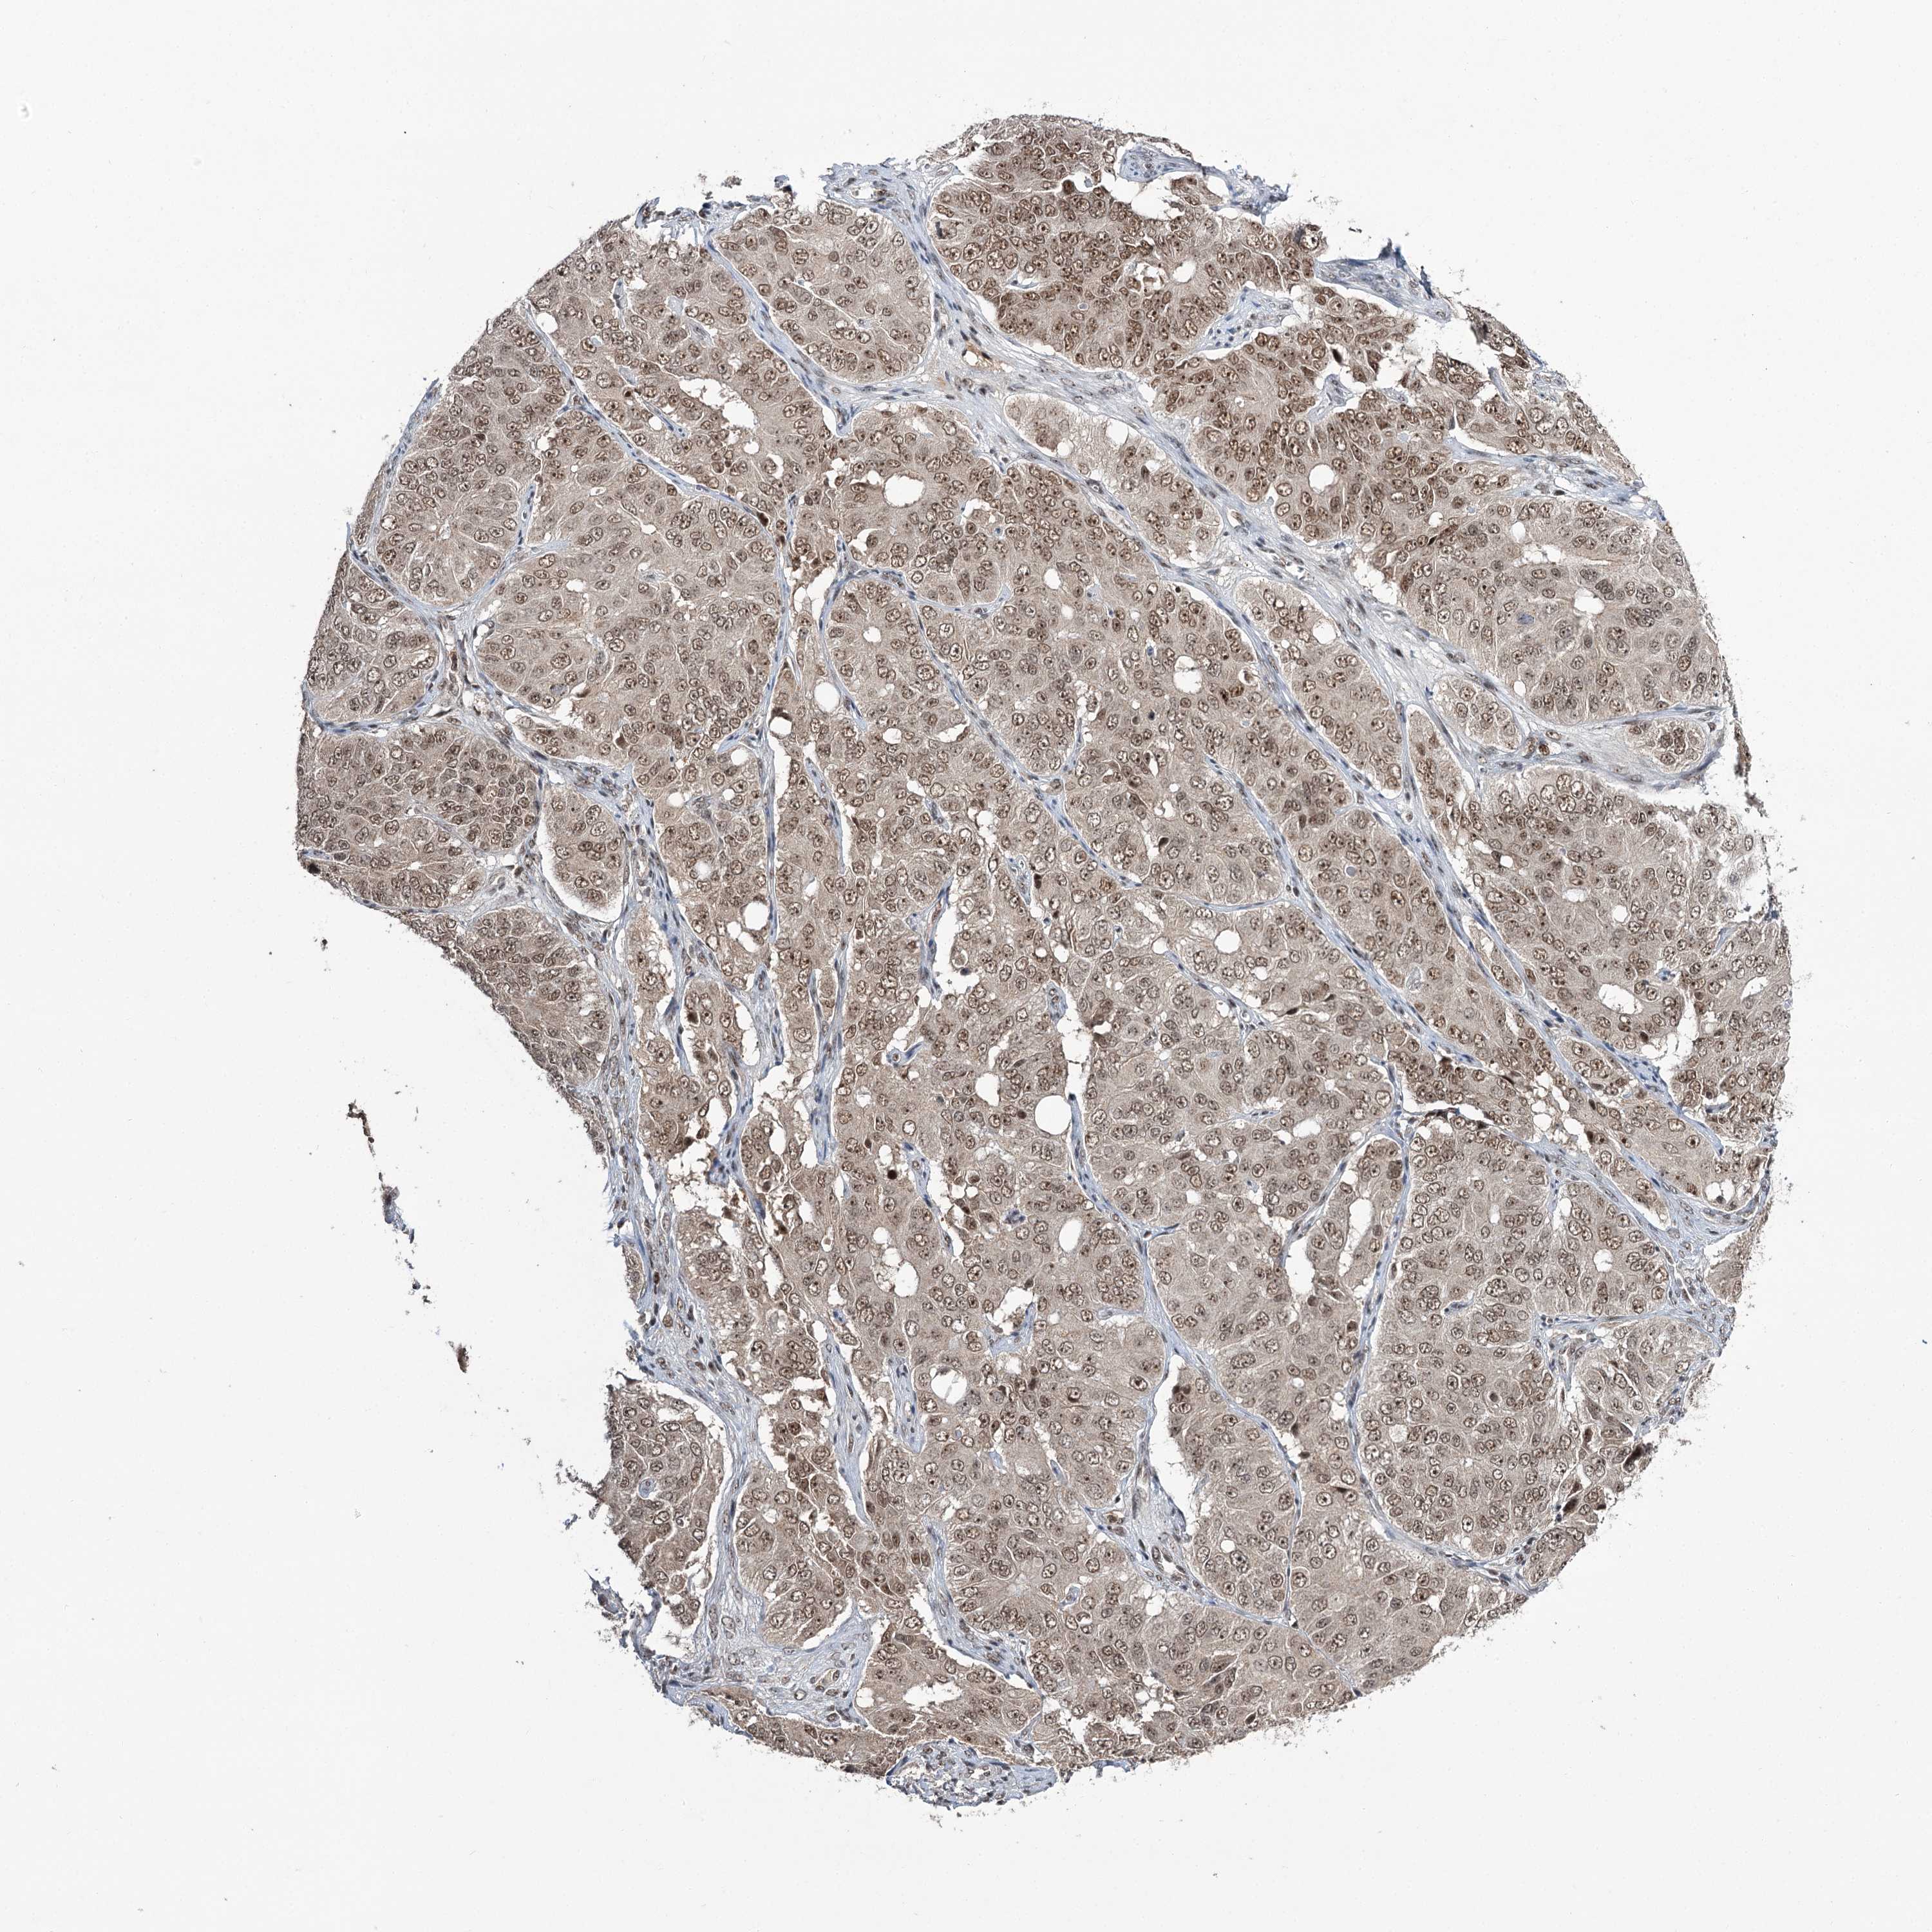

OVARIAN CANCER - Protein expressioni

A mouse-over function shows sample information and annotation data. Click on an image to view it in a full screen mode. Samples can be filtered based on level of antibody staining by selecting one or several of the following categories: high, medium, low and not detected. The assay and annotation is described here.

Note that samples used for immunohistochemistry by the Human Protein Atlas do not correspond to samples in the TCGA dataset.

Antibody stainingi

Antibody staining in the annotated cell types in the current human tissue is reported as not detected, low, medium, or high, based on conventional immunohistochemistry profiling in selected tissues. This score is based on the combination of the staining intensity and fraction of stained cells.

Each image is clickable and will lead to virtual microscopy that enables deeper exploration of all samples and also displays staining intensity scores, fraction scores and subcellular localization as well as patient and tissue information for each sample.

Antibody CAB037153

Staining

High

Medium

Low

Not detected

Intensity

Strong

Moderate

Weak

Negative

Quantity

>75%

75%-25%

<25%

None

Location

Nuclear

Cytoplasmic/membranous

Cytoplasmic/membranous,nuclear

Cystadenocarcinoma, serous, NOS